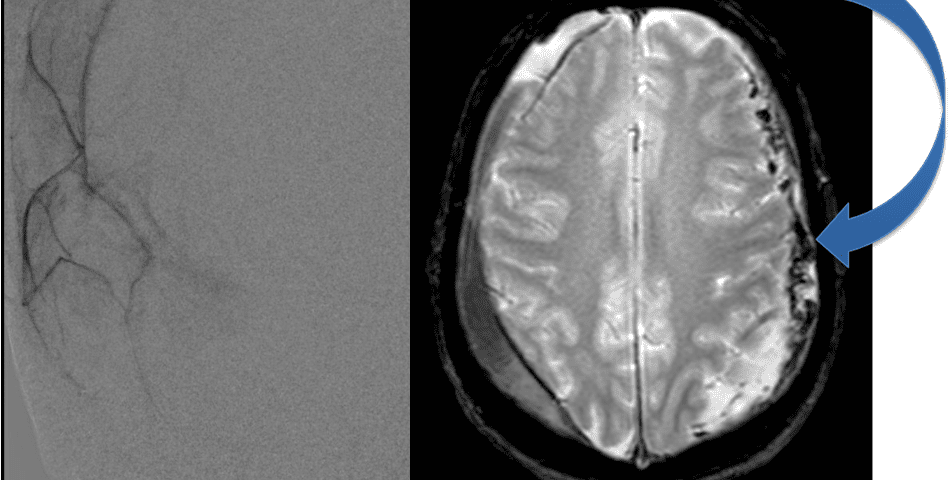

The patient agreed to receive minimally invasive treatment with Bilateral Middle Meningeal Artery Embolization, a new approach to promote resorption of chronic and subacute subdural hematomas in patients that are not improving with conservative measures or have contra-indications to surgical evacuation. Selective catheterization of the Middle Meningeal Artery is followed by transarterial embolization of the territory and inflammatory membranes that are felt to be secreting serosanguinous proteinaceous exceeding the capacity for resorption. MMA embolization was performed bilaterally in this patient. (Figure 2. A and B)

Figure 2. A) Initial right ECA angiogram ; B) Post MMA Embolization; C) Selective Embolization Of Middle Meningeal Artery Membranes using PVA particles (arrows).